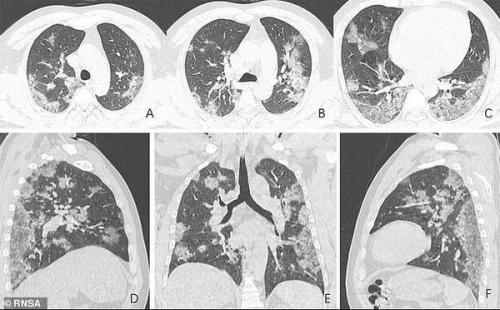

Наиболее характерные признаки пневмонии от Covid-19: множественные помутнения на рентгене (симптом "матового стекла"), утолщение стенок сосудов и периферическое распределение очагов. Все это наблюдается и при "обычной" вирусной пневмонии, но в меньших масштабах.

Снимок легких, зараженной коронавирусом китаянки, публиковал журнал Radiology . 33-летняя женщина с температурой 39 была госпитализирована в городе Ланьчжоу. Рентген показал множественные помутнения, создающие так называемый эффект матового стекла. Второй снимок сделали три дня спустя. На нем видно, что болезнь прогрессирует и область "матового стекла" становится больше.

Легкие 33-летней госпитализированной женщины из Ланчжоу. Фото: Radiology

Аналогичные снимки 44-летнего зараженного мужчины из Китая публиковали и в Радиологическом сообществе Северной Америки . На снимках было видно, как в легких накапливается жидкость, постепенно занимая все больший объем.

Легкие при Covid-19. Фото: rsna.org